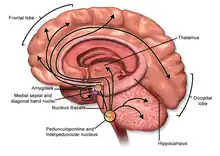

Central nervous system

In the central nervous system, ACh has a variety of effects on plasticity, arousal and reward. ACh has an important role in the enhancement of alertness when we wake up,[13] in sustaining attention [14] and in learning and memory.[15]

Damage to the cholinergic (acetylcholine-producing) system in the brain has been shown to be associated with the memory deficits associated with Alzheimer's disease.[16] ACh has also been shown to promote REM sleep.[17]

In the brainstem acetylcholine originates from the Pedunculopontine nucleus and laterodorsal tegmental nucleus collectively known as the mesopontine tegmentum area or pontomesencephalotegmental complex.[18][19] In the basal forebrain, it originates from the basal nucleus of Meynert and medial septal nucleus:

- The pontomesencephalotegmental complex acts mainly on M1 receptors in the brainstem, deep cerebellar nuclei, pontine nuclei, locus coeruleus, raphe nucleus, lateral reticular nucleus and inferior olive.[19] It also projects to the thalamus, tectum, basal ganglia and basal forebrain.[18]

- Basal nucleus of Meynert acts mainly on M1 receptors in the neocortex.

- Medial septal nucleus acts mainly on M1 receptors in the hippocampus and parts of the cerebral cortex.

In addition, ACh acts as an important internal transmitter in the striatum, which is part of the basal ganglia. It is released by cholinergic interneurons. In humans, non-human primates and rodents, these interneurons respond to salient environmental stimuli with responses that are temporally aligned with the responses of dopaminergic neurons of the substantia nigra.[20][21]